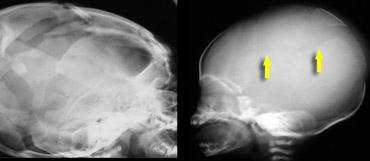

Mặc dù xuất huyết có thể xảy ra ở bất kỳ vị trí nào, máu có xu hướng lan vào khe liên bán cầu (mũi tên trên hình bên phải).

Hình ảnh

Máu tụ dưới màng cứng tăng tỷ trọng vùng đỉnh trái và máu tụ dưới màng cứng nhỏ vùng trán-đỉnh phải lan vào khe liên bán cầu.

TRÁI: Gãy xương kiểu vỏ trứng ở một trẻ tử vong do chấn thương não sau khi bị ném từ trên cao. PHẢI: Gãy xương sọ ở trẻ bị lạm dụng.

Gãy xương sọ

Gãy xương sọ là chấn thương thường gặp trong lạm dụng trẻ em, nhưng cũng phổ biến trong chấn thương do tai nạn.

Các hình thái gãy xương sọ gợi ý lạm dụng trẻ em bao gồm:

- Gãy xương nhiều mảnh kiểu “vỏ trứng”

- Gãy lún xương chẩm

Hộp sọ của trẻ sơ sinh khá đề kháng với chấn thương, vì vậy bất kỳ gãy xương nào không phù hợp với bệnh sử đều cần đặt ra câu hỏi về chấn thương không do tai nạn.